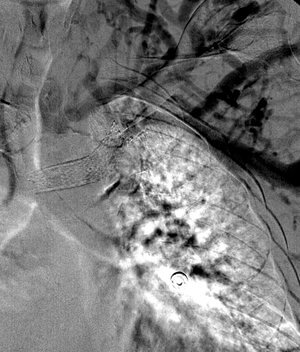

35 year old male patient with CKD requiring hemodialysis via a LUE AV graft. He presents with left upper extremity swelling secondary to a left brachiocephalic vein occlusion.

Comment: This chronic occlusion was treated with stent placement. Unfortunately, the stent occluded within months of placement, necessitating placement of additional stents. This happened again a few months later, requiring angioplasty and covered stent placement.